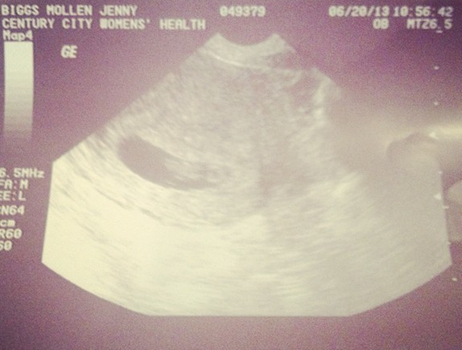

The actress shared this snap on her Instagram account this week.

Mollen also confirmed the news with a number of pictures on her Instagram account including one showing positive pregnancy tests as well as one of her sonogram beside which she wrote: “My new assistant is so f**king lazy!”